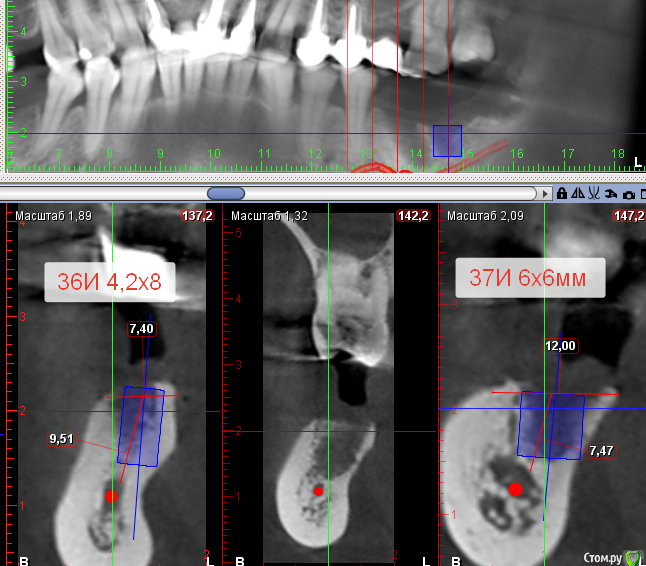

Sergiosse Опубликовано 22 мая, 2017 Поделиться Опубликовано 22 мая, 2017 Коллеги, какой ваш опыт использования таких имлантов 6х6мм на нижней челюсти. От НКР пациент отказалась, хочет только импланты.Я нашел такие у Dentis. Ссылка на комментарий

Sergiosse Опубликовано 22 мая, 2017 Автор Поделиться Опубликовано 22 мая, 2017 До нерва 7,5 мм. Мне нужен 6 миллиметровый имплантант. Я бы рад взять его с меньшим диаметром ,но есть только 6 мм. Ссылка на комментарий